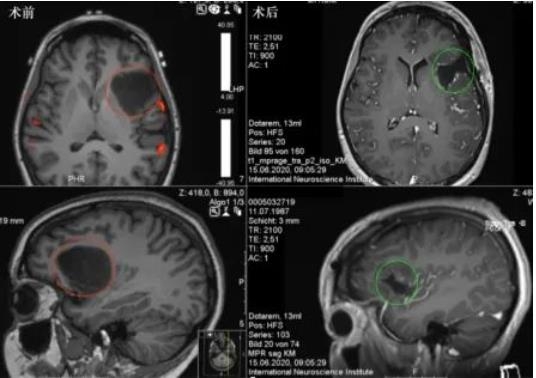

术前术后影像资料:

图:术前MR显示岛叶占位,直径约为4cm,紧邻重要脑功能区,包绕左岛叶的大部分,并在背侧延伸至岛叶的后部。术后MR显示肿瘤全切,无

脑出血、水肿等正常脑组织损伤。